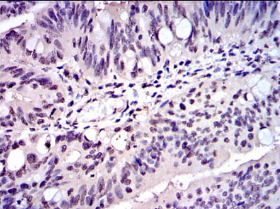

IHC    1/200 - 1/1000